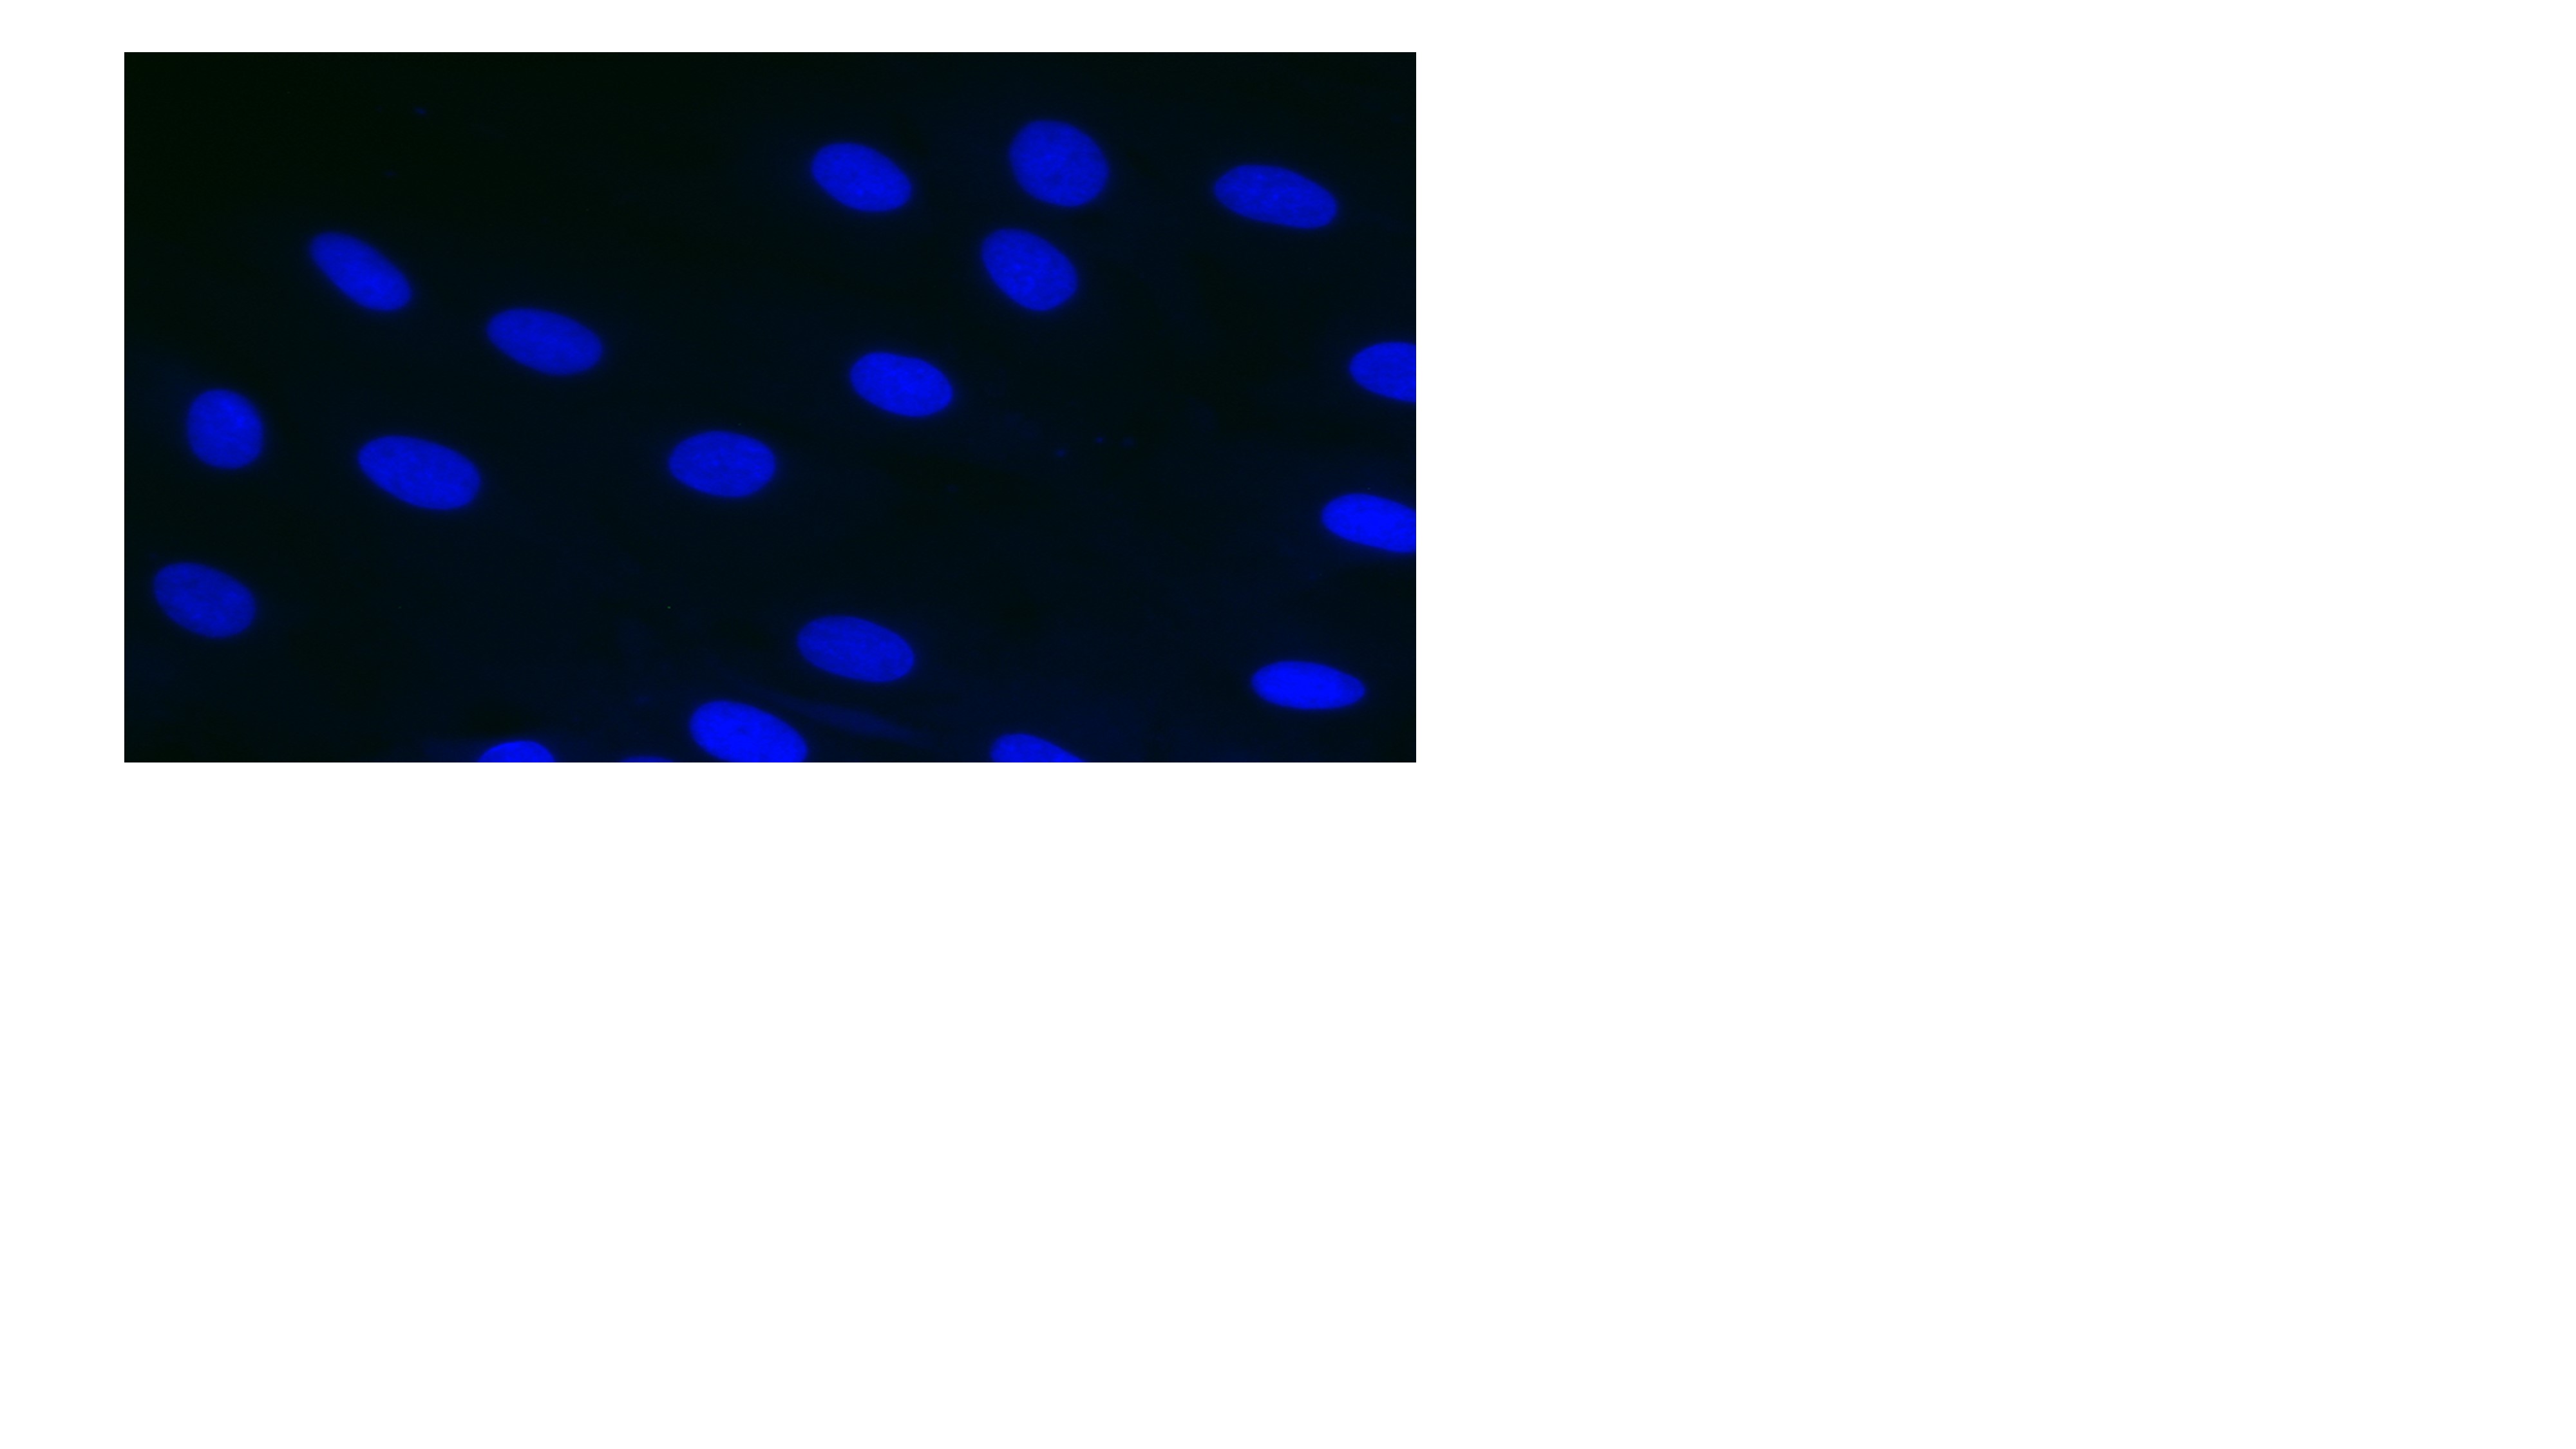

Images show DM1 cells treated:

We are now at the stage where we know if we can inhibit CDK12 selectively - then it's going to be a potential therapy - and now we are trying to work out how to do that."